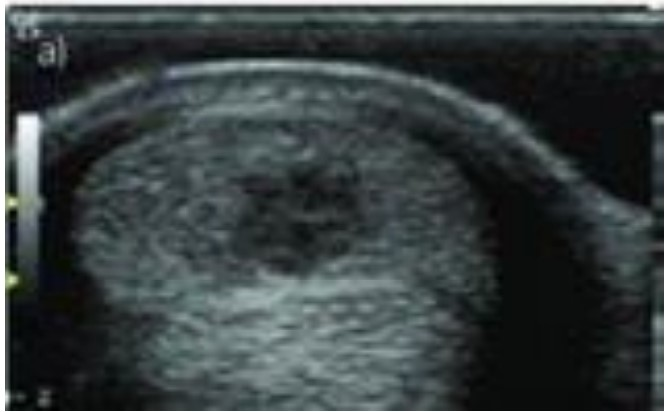

O exame ultrassonográfico dos tendões e ligamentos dos equinos é importante na identificação de lesões e na avaliação da efetividade do tratamento. Observe a imagem abaixo e assinale o enunciado CORRETO que se refere à estrutura anatômica acometida e o diagnóstico.

Enunciado 4583264-1

Fonte: Alzola, R. et al. Ultrasonographic-based predictive factors…. Equine Veterinary Journal. 50. 10.1111/evj.12810.